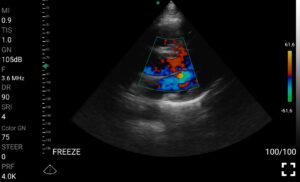

• Doppler καρδιακών βαλβίδων: Βασική εκτίμηση στένωσης/ανεπάρκειας.

Παραδείγματα

Ολες οι παραπάνω απεικονιστικές εξετάσεις έχουν ληφθεί από φορητή συσκευή όπως: Apple Iphone, Tablet, Samsung Mobile Phones και διάφορες άλλες φορητές συσκευές.